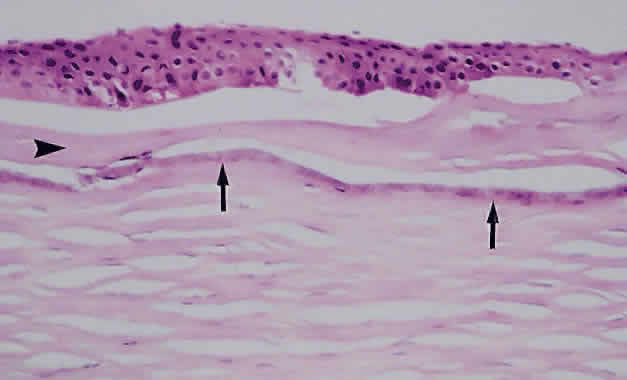

Much attention has been given to the histopathologic nature of the “snowbanks,” which has been studied by both light and electron microscopy.52,54,56–58 These fibrovascular-glial proliferations are found over the inferior pars plana and peripheral retina. They are composed of dense connective tissue derived from condensed, collapsed vitreous and often are vascularized. These vessels may reveal features of high endothelial venules (Fig. 8). Such endothelia are known to play a role in the homing of activated lymphocytes.54 The cellular elements of these membranes include fibroglial cells that are believed, based on their electron microscopic characteristics, to represent fibrous astrocytes, as well as nonpigmented ciliary epithelial cells, fibroblasts, and lymphocytes (Fig. 9).52–55,59,60 The vitreous is infiltrated by chronic inflammatory cells, and despite the nongranulomatous nature of the inflammatory component in the snowbanks, vitreous snowballs have been reported to consist of epithelioid cell granulomas.52

Fig. 9. A. Photomicrograph of “snowbank” in patient with pars planitis showing a fibroglial mass with proliferated epithelial elements (hematoxylin and eosin; × 31). B. Higher magnification showing epithelial elements and glial proliferation (hematoxylin and eosin; × 80). C. Chronic inflammatory cell infiltrate in pars planitis (hematoxylin and eosin; × 200).